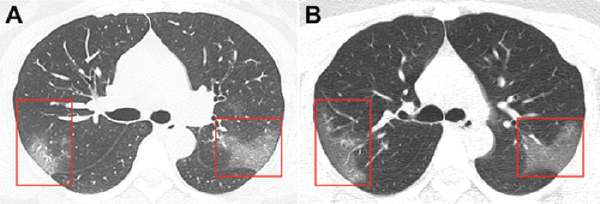

“Radiology” журналида чоп этилган суратлар компьютер томографияси натижасида Хитойнинг Ланчжоу шаҳрида 39 даража ҳарорат билан шифохонага ётқизилган 33 ёшли аёлдан олинган.

Биринчи суратда “жилосиз ойна” таассуроти туғдирувчи хиралашишлар кўрсатилган. Уч кун ўтиб олинган иккинчи суратда зарарланган соҳа кенгайганини кўриш мумкин.